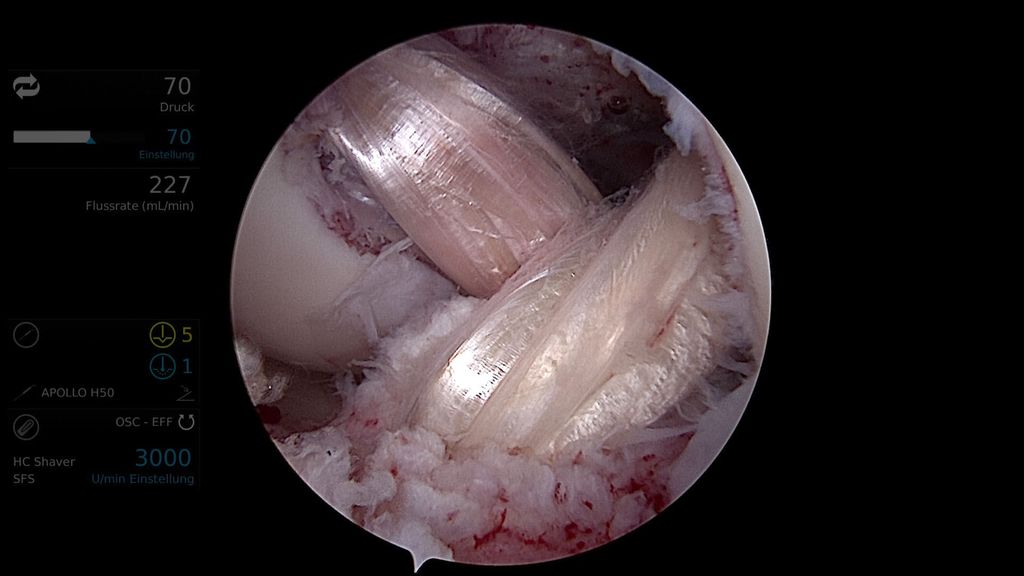

In der Regel wird bei multiligamentären Kniegelenksverletzungen zweizeitig vorgegangen. Hierbei werden primär, innerhalb von 2 Wochen, der mediale und der laterale Bandkomplex (periphere Pfeiler) und sekundär nach ca. 6–8 Wochen das VKB und HKB mittels Auto- oder Allograft rekonstruiert (Abb.3, 4).12